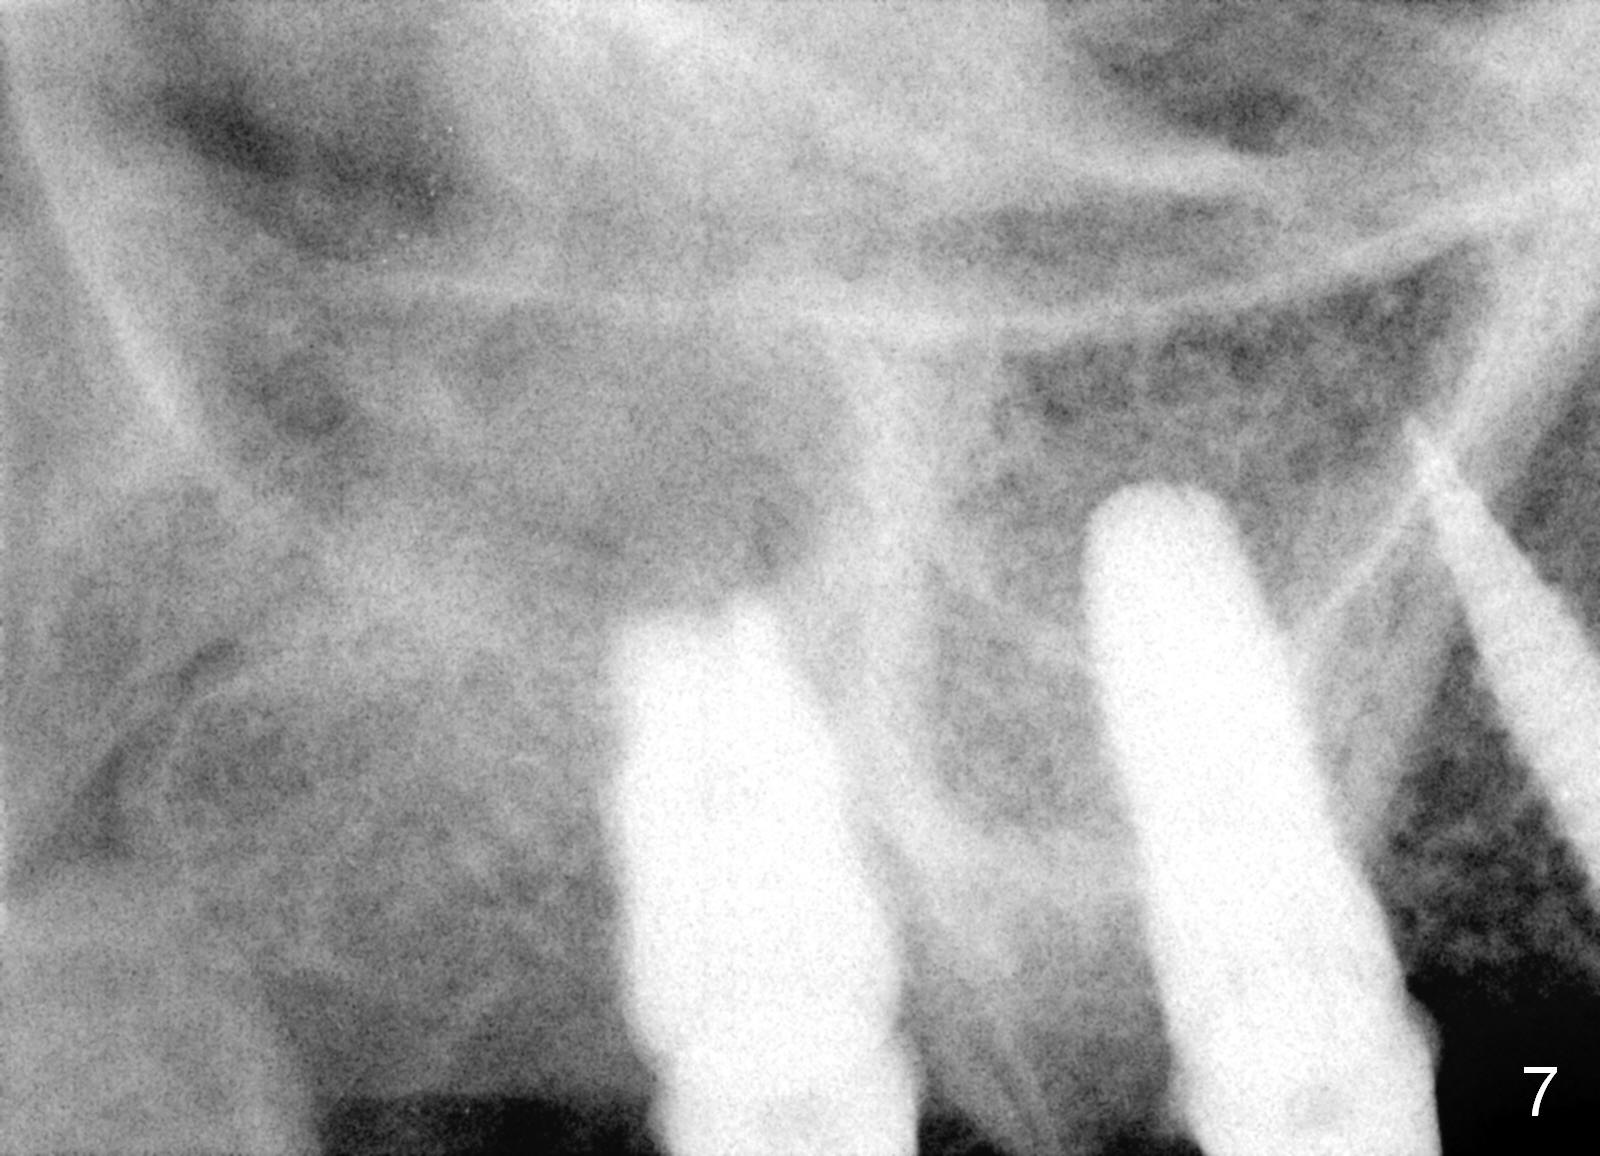

Provisional bridge is fabricated after wound healing.  Four months postop, there is minimal bone resorption at the site of #5 (Fig.7,8).  Single-unit crowns are fabricated.